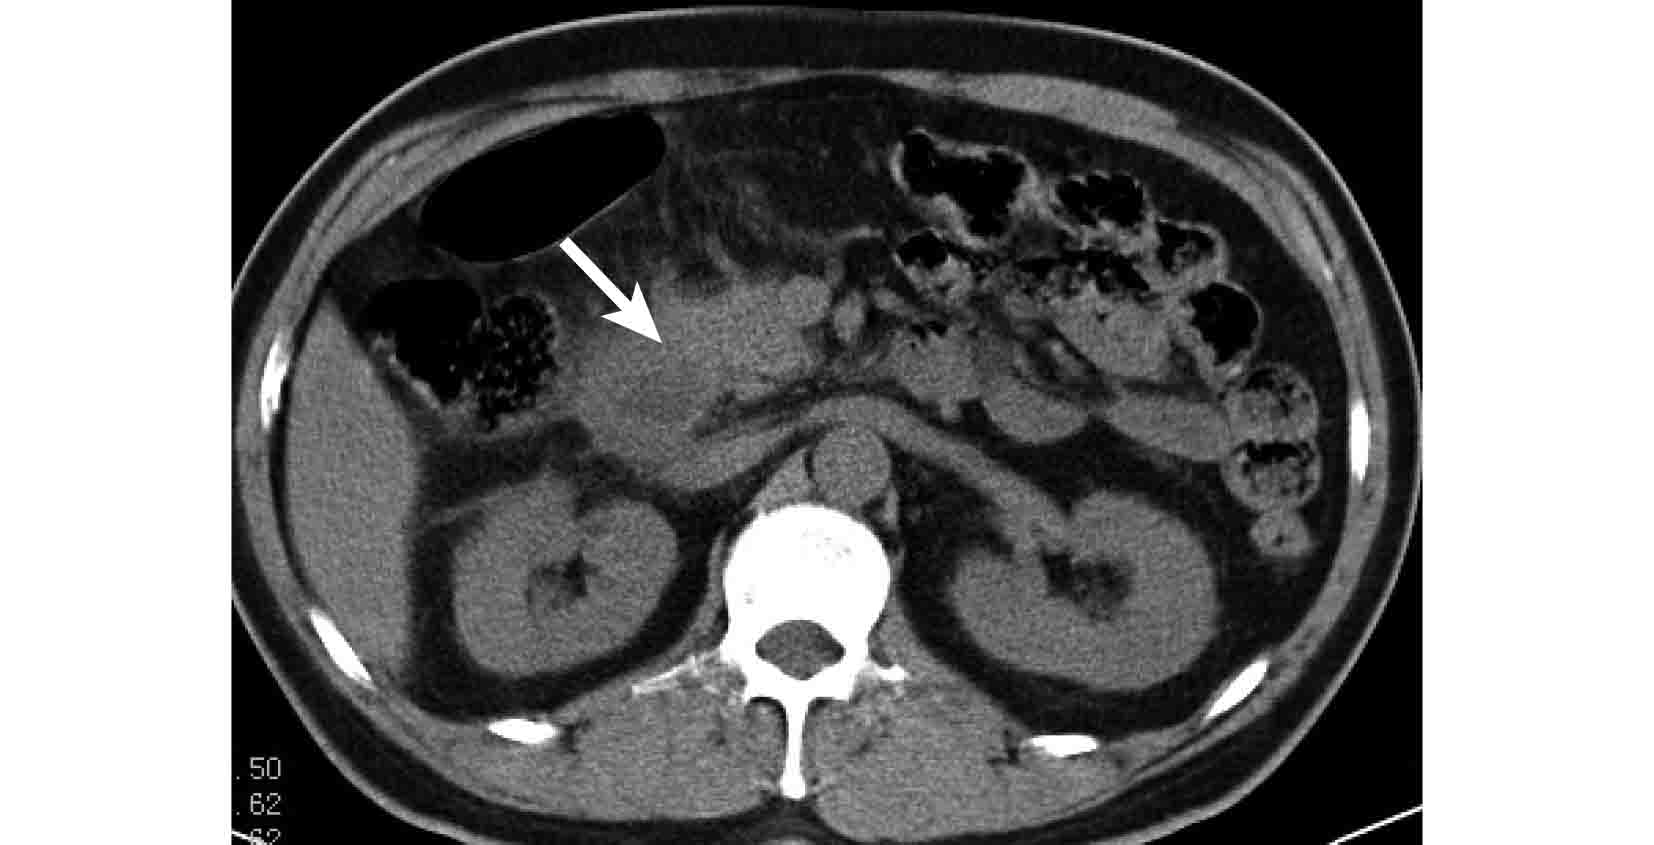

圖1

十二指腸降段炎及其擴散情況 CT 像 降段壁增厚,鄰近橫結腸系膜腫脹(白箭)